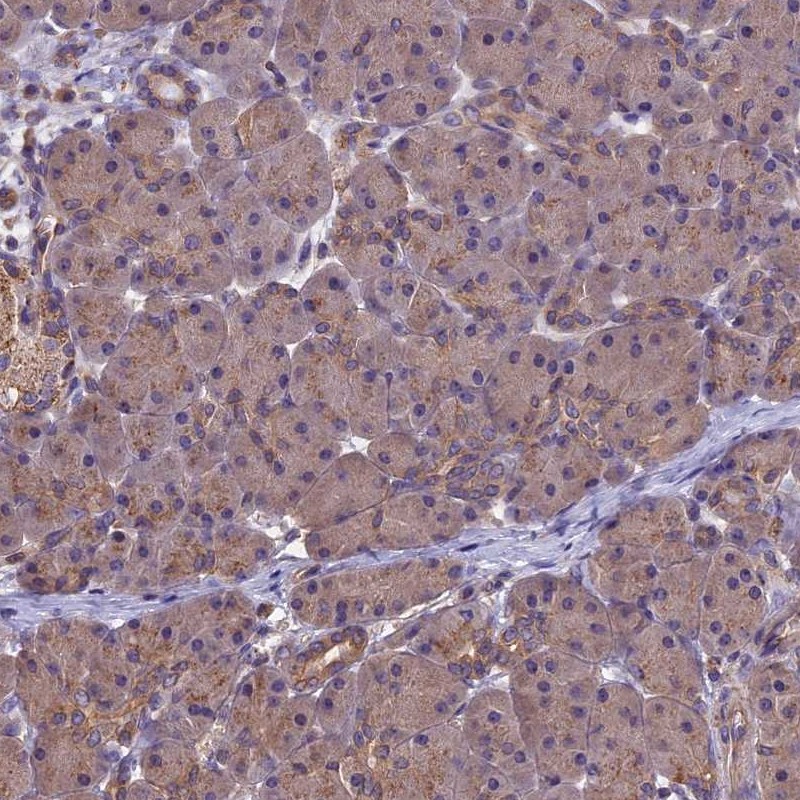

Immunohistochemistry analysis in human thyroid gland and pancreas tissues using Anti-CHMP2A antibody. Corresponding CHMP2A RNA-seq data are presented for the same tissues.